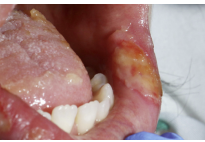

Mucosal pressure ulcer

These develop on mucosal membranes such as the tongue, mouth, nasal passages, genitals and rectum.

Area may be painful, changes in temperatures and texture may be present.

Mucosal tissue does not have the same layers of skin as rest of the body so it cannot be graded and should be documented as a mucosal pressure ulcer.

Pressure damage is often caused by devices such as catheters, tubing, orthotic appliances or any objects which are in prolonged contact with the skin.